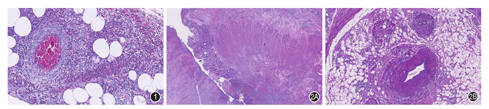

组织学特点为增生的纤维组织取代动脉壁的正常结构,使管壁狭窄、增粗,从而导致急性或慢性肠壁缺血。基于主要病变所在的层次将FMD组织学分类为:(1)内膜纤维增生型:少见,以局灶偏心性或向心性内膜下纤维组织增生为特点;(2)中膜纤维增生型:最常见(占70%),中膜平滑肌被不同程度增生的纤维组织取代(图4);血管造影表现为血管壁增厚的狭窄区和血管平滑肌缺失的扩张区相间分布形成经典的"串珠状"改变;(3)中膜旁纤维增生型:次常见,中膜和外膜间的弹力纤维环周状沉积;(4)中膜增生:少见,相对正常的动脉中膜平滑肌的明显增生伴有轻微结构破坏;(5)外膜纤维增生:胶原纤维环绕动脉外膜,并延伸至动脉旁纤维脂肪组织[21,22]。

IMHMV是一种罕见的以肠系膜静脉非炎性肌内膜增生为特点的血管病变。一般发生于中青年男性,好发于乙状结肠[26],也可累其他肠段。其病因尚不明确,可能与机械性损伤有关[27]。IMHMV的临床表现和内镜表现与CD相似,依靠手术切除标本鉴别。组织学特征为肠系膜中小静脉内膜的增生、甚至闭塞,而没有静脉周围炎和伴行动脉的累及(图5)。肠黏膜可见慢性肠缺血[28]。外科切除病变肠管后一般不会复发。

IMP是一种以结肠静脉弥漫性钙化和闭塞为特点的缺血性肠病,大多发生在亚裔人,其发病与服用含栀子苷的中草药(如栀子花果)有明确的相关性[29]。临床表现主要为肠梗阻,主要累及右半结肠。腹部平片和CT具有重要的诊断价值,腹部平片的经典表现为右下腹多发条纹状钙化,腹部CT表现为结肠壁增厚和受累肠系膜静脉分支的钙化,而CT小肠造影(CTE)有助于精准定位病变血管[30]。肠镜表现为暗紫色水肿僵硬黏膜,也可见糜烂、溃疡和管腔狭窄。组织学表现为肠壁大量血管增生,毛细血管及静脉管壁增厚、玻璃样变性,伴钙化(图6)。严重者肠壁固有肌层显著增厚、广泛玻璃样变性,黏膜可见缺血改变[30]。停用中药是首选治疗手段,严重者需切除病变肠管。

肠系膜动静脉发育不良/血管病(mesenteric arteriovenousdysplasia/vasculopathy,MAVD/V)是新提出来的一种非炎性、非动脉粥样硬化性血管病,可同时累及肠系膜动脉和静脉,主要见于中老年女性,多发生在回肠和结肠,可单发或多发。慢性腹痛是最常见的症状。不同于肠系膜FMD累及肠系膜上动脉和腹腔动脉这样中等大小血管,MAVD/V累及紧邻肠壁的更小管径的肠系膜血管,故常规的影像学手段不能检查到血管异常。主要组织学特点包括:(1)平滑肌呈向心或偏心状围绕动脉和静脉中膜,且至少为2个病灶;(2)不同程度的内膜和中膜增生和外膜纤维化;(3)缺乏炎症反应和血栓(图7)。其余组织表现可类似于慢性肠炎或缺血性肠病[31]。外科手术切除可治愈。